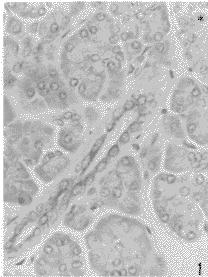

镜下观察发现,胰腺小叶间导管、小叶内导管上皮细胞均呈IAPP免疫反应性,免疫反应产物呈棕黄色,主要位于核上方和两侧(图1),至闰管上皮和泡心细胞阳性染色减弱呈浅黄色(图2)。同一胰腺切片中,胰岛IAPP-IR细胞呈色强度较小叶内导管上皮弱,似闰管上皮呈浅黄色(图1)。观察邻片同一部位的IAPP和胰岛素免疫组织化学染色结果,同一小叶内导管上皮IAPP为弱阳性(图3),但未见胰岛素免疫染色,而胰岛内及散在于腺泡和导管上皮细胞之间的Ins-IR细胞呈深棕色(图4)。

图1 正常成人胰腺小叶内导管上皮细胞呈IAPP阳性染色,示胰岛的一部分。免疫组织化学PAP法,Mayer苏木精复染细胞核(以下同) ×400